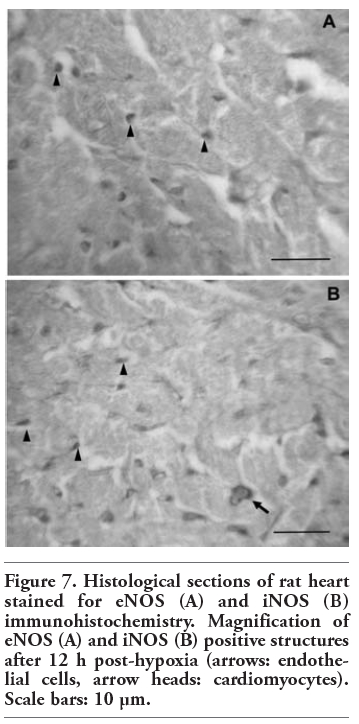

In all the experimental groups, eNOS immunoreactivity was detected in vascular endothelial cells and cardiomyocytes (Figure 5). As reflected in Figure 6, no iNOS immunoreactivity could be detected in the control group. Nevertheless, iNOS-positive staining appeared in the myocardium after hypoxia (0 h, 12 h, 5 days). Here, we show only the most representative images of eNOS and iNOS tissue location, corresponding to 4 of the 8 experimental groups. Magnification of eNOS and iNOS positive structures is shown in Figure 7, in order to allow easily identifying eNOS and iNOS immunoreactive cells.

Figure 7. Histological sections of rat heart stained for eNOS (A) and iNOS (B) immunohistochemistry. Magnification of eNOS (A) and iNOS (B) positive structures after 12 h post-hypoxia (arrows: endothelial cells, arrow heads: cardiomyocytes). Scale bars: 10 µm.